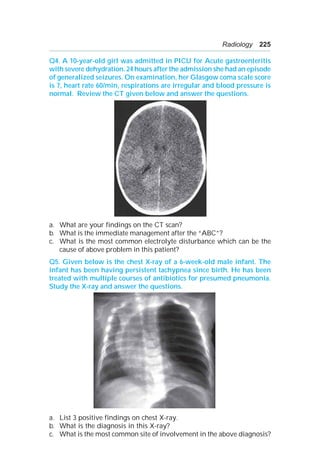

A 11:

a. Oesophageal foreign body.

b. Oesophageal perforation.

Oesophageal obstruction.

Tracheal compression.